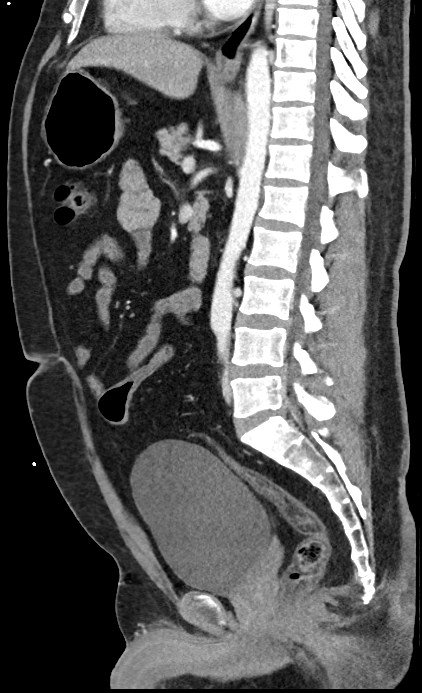

The Sagittal View

This is also derived from another Latin word sagitta meaning “arrow”. A sagittal view follows the plane of the sagittal suture of the skull which run from the front of the skull to the back. In fact, if you look closer, it does looks like an arrow.

This view is useful for assessing anatomical structures with a vertical orientation like the spine, or front-to-back orientation like the central brain, providing important diagnostic details not seen in axial or coronal views.